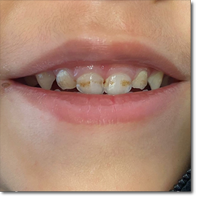

Niño de 3 años que acude a consulta por presentar desde hace largo tiempo manchas en los dientes...

Álvarez García J, Sáez López E, Sánchez Durán MA.

30 septiembre 2025

Valoración